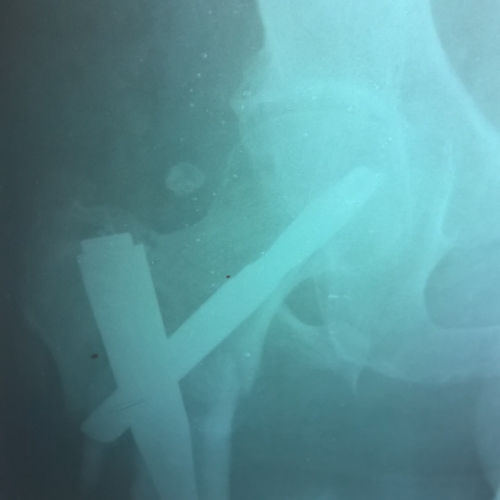

Современная методика лечения переломов бедренной кости - система PFNA (Proximal Femoral Nail Antirotation)